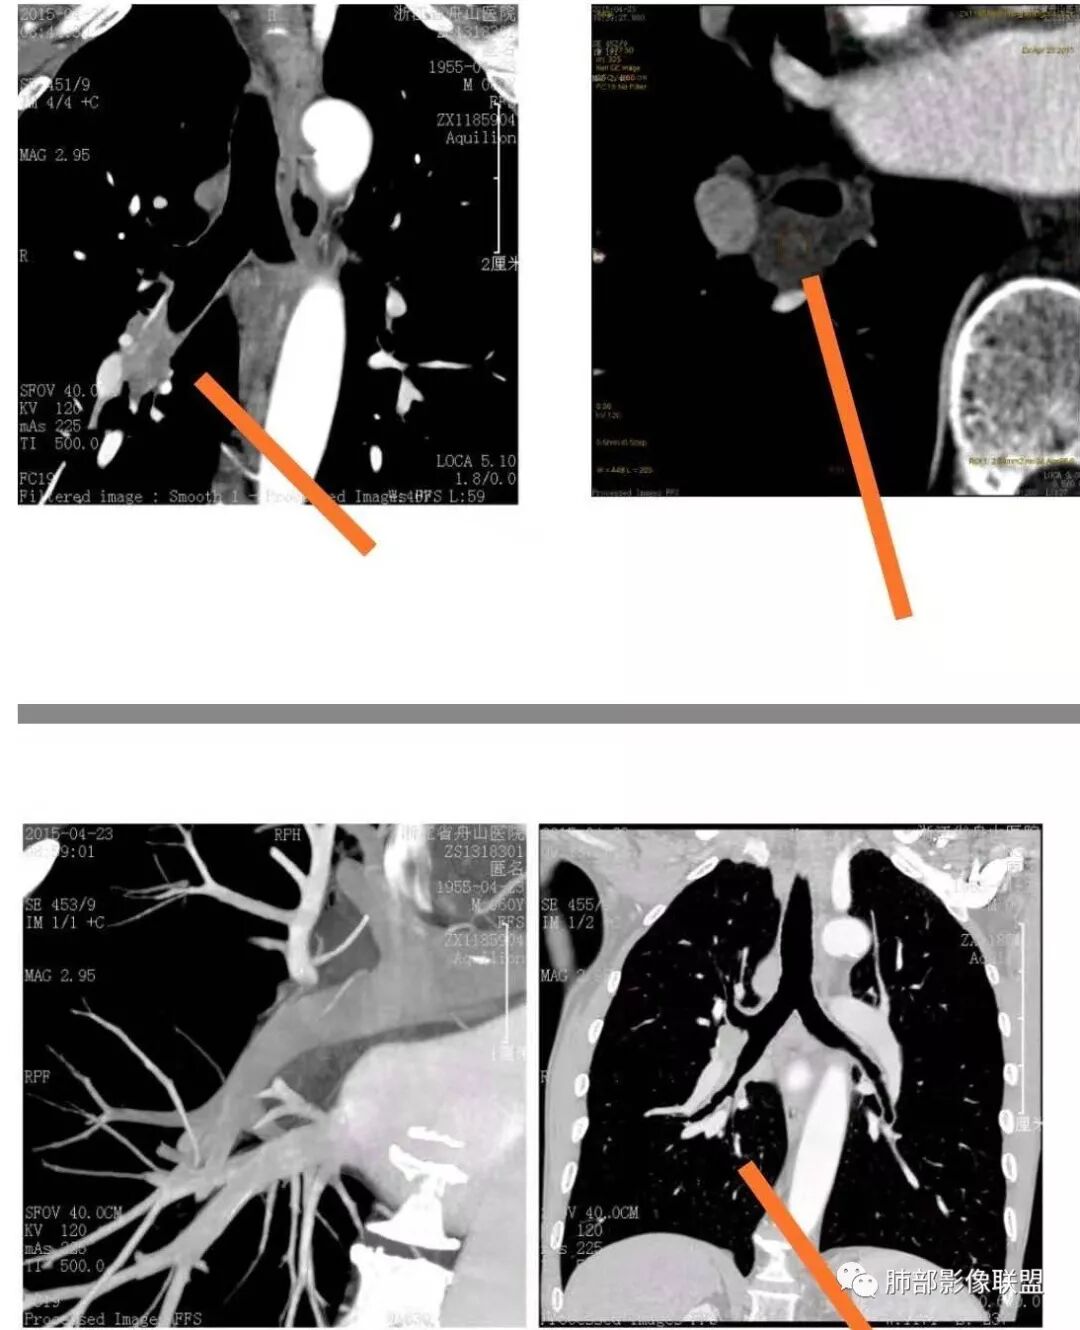

右肺下叶支气管开口新生物,轴位管腔及纵向基底干大部分受累狭窄,支气管管壁破坏明显,强化较低不均匀,肺门、7组、4R淋巴结肿大,考虑恶性支气管腔内肿瘤,鳞癌可能性大,需要与类癌、涎腺类肿瘤鉴别

老年男性,60岁,右下肺门肿块,右下支气管粘膜下生长,并堵塞,无明显阻塞性肺炎和肺不张,早期多发淋巴结转移,似不均匀强化。综合看恶性程度高,考虑大细胞癌,一个不支持点,大细胞癌外周多见。

男,60岁,右肺下叶支气管开口新生物,轴位管腔及纵向基底干大部分受累狭窄,支气管管壁破坏并突破形成腔外肿块,强化较低不均匀,右肺门、7组、4R淋巴结肿大,考虑恶性没问题,鳞癌可能性大,类癌、粘液表皮样癌,乳头状瘤待排。

右肺下叶支气管不规则软组织肿块,病灶沿支气管生长,有一定的张力,部分包绕支气管壁,增强病灶内可见中度强化,内部有延迟强化的特点,周围淋巴结增大,诊断恶性病变无疑,远端无明显支气管阻塞,主要考虑粘液表皮癌,腺样囊腺癌,鳞癌之间鉴别,病灶有类似神经源性病变生长方式,腺样囊腺癌,其次考虑鳞癌或粘液表皮癌。